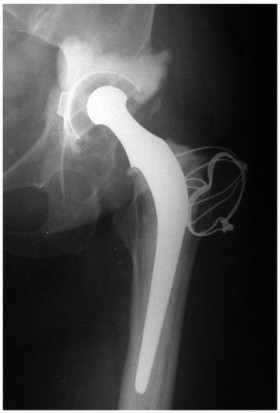

Principles, Planning, and Decision Making Revision total hip arthroplasty is complex and demanding. The stake…

Extended Trochanteric Osteotomy BACKGROUND P. Maxwell Courtney Wayne G. Paprosky Removal of well-fixed femora…